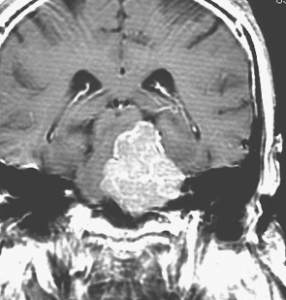

典型的な髄膜腫

この髄膜腫は中程度の大きさのものです。円蓋部髄膜種という最も多い最も手術の簡単なタイプです。麻痺や失語症やてんかんなどの症状はありません。とても美しくて若い女性の髄膜腫でしたが,子供に遺伝はしませんし,癌などと違ってタバコなどこれといった原因がなくて発生するものです。

最も見やすいのが,ガドリニウム造影剤を注射して撮影するものです。一般的に髄膜腫は造影剤で白く映し出されます。この腫瘍は左脳側にあります。MRIの軸面という輪切りの写真では左右が逆になりますから注意してください。脳を下から見た図になっています。MRIはいろいろな方向から腫瘍を見ることができますが,右は冠状断という正面から見た図です。よく見ると腫瘍の上と下のはじっこに線状に糸を引いたように造影される部分があります。これをテールサイン(しっぽのサイン)といいます。腫瘍が硬膜に沿って延びている可能性があることを示しています。